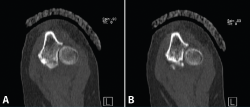

Presentamos el caso de una mujer de 46 años, diestra, sin patología crónica y que trabaja como auxiliar en una residencia geriátrica. Durante su jornada laboral sufre una caída casual presentando dolor y limitación funcional en su codo izquierdo. No presenta deformidades externas en el codo, ni lesiones vasculonerviosas. En el estudio radiológico, se sospecha una fractura de la punta de la apófisis coronoides del codo izquierdo, que correspondería, según la clasificación de Regan y Morrey, al tipo 1 (Figuras 1 y 2). Se comprueba que el codo es estable y se coloca una férula braquial, a la espera de realizar una tomografía computarizada (TC), que confirma la lesión. En la TC podemos visualizar mejor la morfología de la fractura de coronoides tanto en los cortes sagitales (Figura 3), como en los axiales (Figura 4).

Figura 3. Corte sagital de tomografía computarizada, realizado a los 10 días de la lesión. Vemos enmarcada la línea de fractura al nivel de la punta de la apófisis coronoides.

Figura 4. Cortes axiales de tomografía computarizada a los 10 días de la lesión. A: fractura de la punta de la coronoides que se extiende hacia la base de la coronoides; B: fractura conminuta al nivel de la faceta anteromedial de la coronoides.